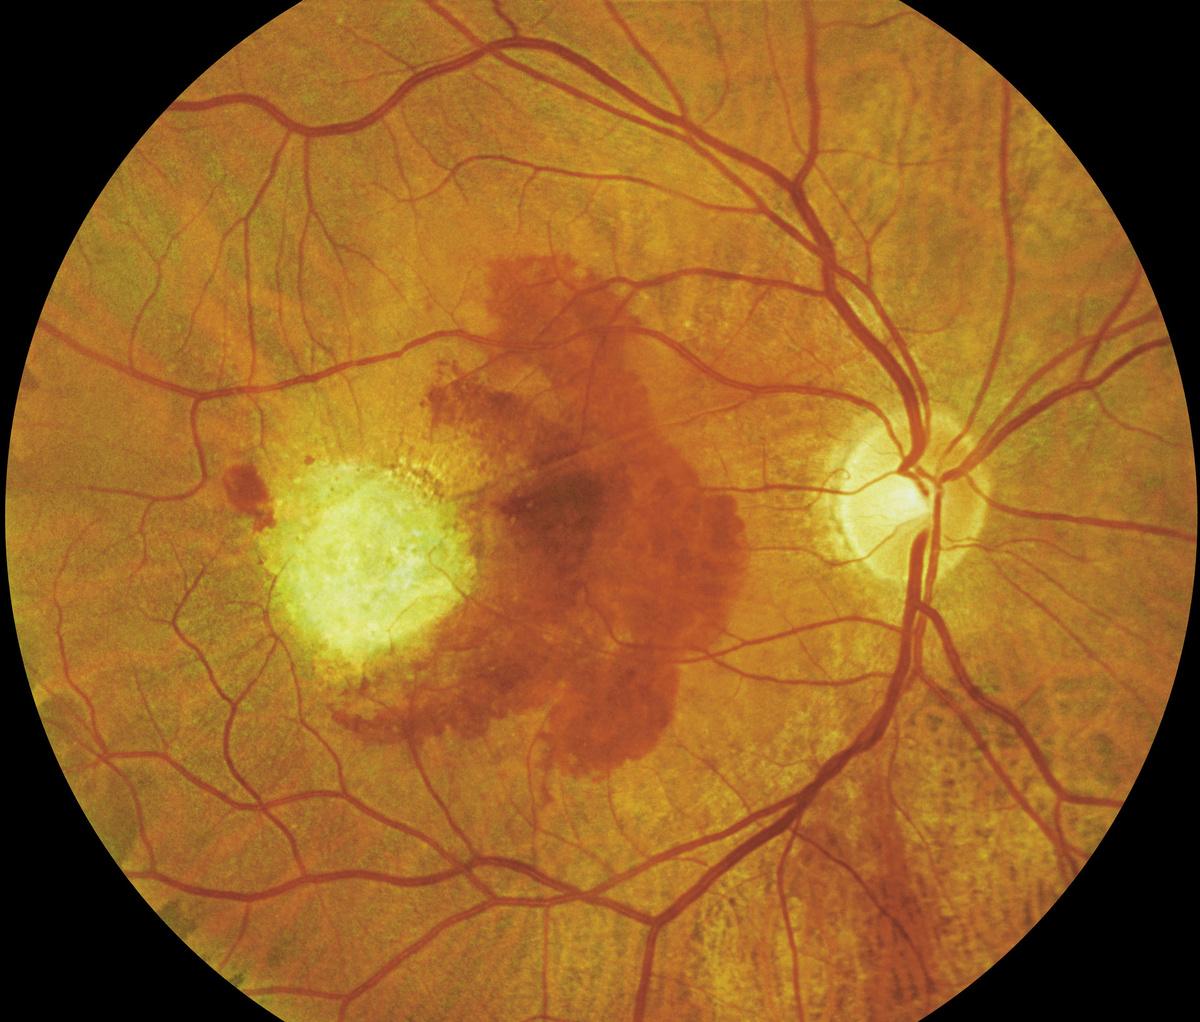

Возрастная макулярная дегенерация / Gettyimages.ru / BSIP / UIG

При ВМД снижается острота зрения, пациенту становится трудно читать и распознавать лица людей, а также определять расстояния. Особенно страдает центральное зрение: больной может видеть перед собой тёмное пятно и различать предметы только периферическим зрением.

Есть сухие формы макулодистрофии, но существует и влажная форма, когда под сетчатку через повреждённые пигментные эпителии прорастают неполноценные сосуды, которых там быть не должно. Они пытаются взять на себя функции отмирающих сосудов, но вместо этого вызывают осложнения: могут кровоточить и давать отёки. При влажной, отёчной форме ВМД острота зрения резко снижается — и человек может ослепнуть буквально в одночасье.